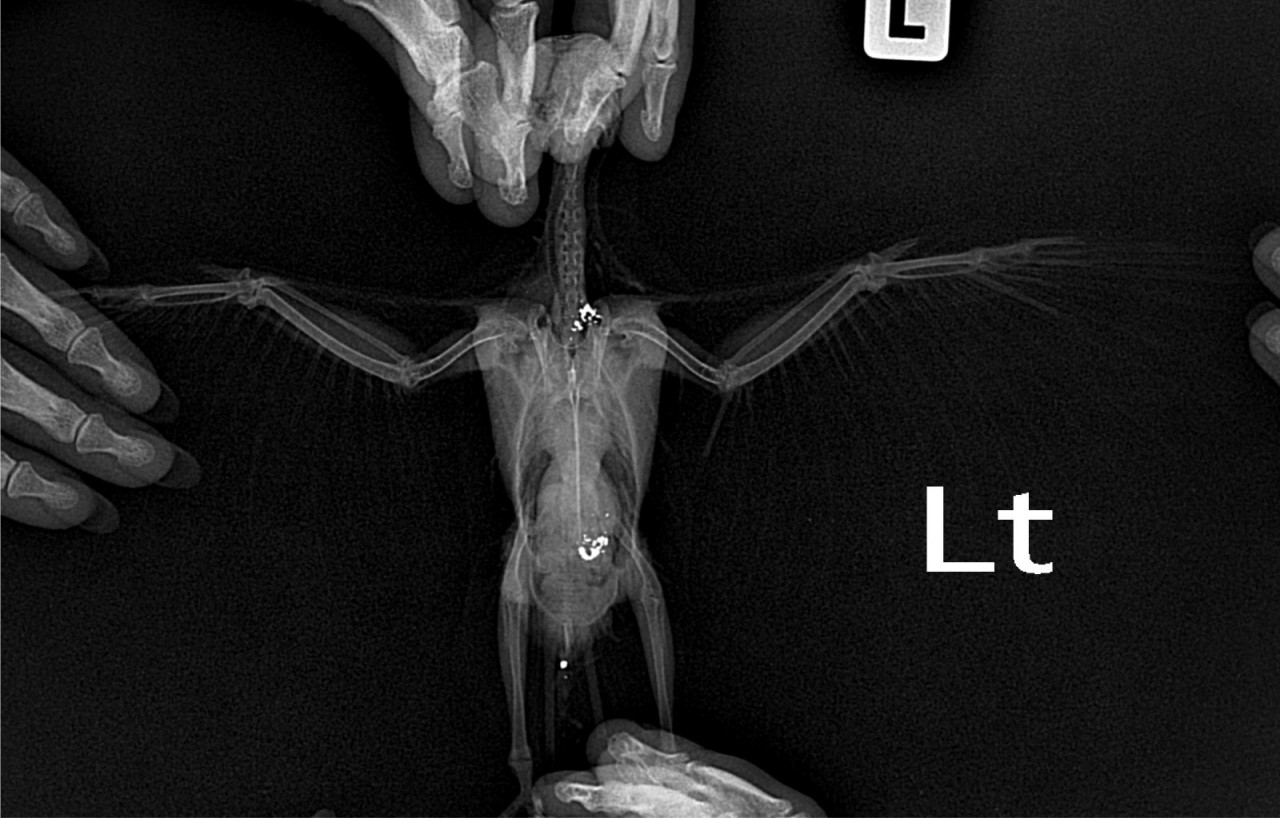

Добрый день. Корелле 10 мес., волнистику 6 мес. Ползали с утра возле балконной двери и что-то собирали там. К вечеру у кореллы началсь рвота кормом, слабость, понос. На утро совсем был плох, просто сидел с закрытыми глазами, волнистик еще был шустрым. Съездили к орнитологу с кореллой, сделали снимок, на снимке увидели пенвмонию, еще там были белые камушки, на что врач сказал, что это еда. Я не поверила, отправила результаты рентгена другому специалисту, она сказала, что отравление свинцом, что еда не отображается на рентгене. Срочно искать пробирки, разводить их физрастовром и давать попугаям. У волнистка уже начаись тоже симптомы (рвота и понос). Первый орнитолог выписал суммамед и неболин. Второй - пробирки с физ.раствором, дюфалак, сам физ.раствор по 1 мл - 5 раз в день. Кормим кашками. Стало немного лучше после одного дня лечения. Что у нас в итоге-то, хочу послушать других специалистов. Рентген прилагаю.

Здравствуйте. На рентгене действительно видны яркие рентгенплотные включения в проекции зоба или желудка, что нехарактерно для обычного корма и скорее всего указывает на инородные тела с содержанием металла, возможно свинец или цинк.

Также видны признаки пневмонии

это усиление лёгочного рисунка и возможно наличие воспалительного инфильтрата.

Симптомы (рвота, понос, слабость, у обоих птиц одновременно) подтверждают токсическую природу. Еда на рентгене действительно не отображается, так что второй специалист прав.